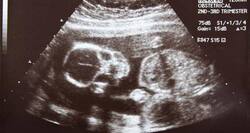

The practice of examining pregnant women using ultrasound is called obstetric sonography, and is widely used. In physics, 'ultrasound' refers to sound waves with a frequency too high for humans to hear. The sound reflects and echoes off parts of the tissue; this echo is recorded and displayed as an image to the operator.

Ultrasound During Routine Prenatal Care: What To Expect During Different Scans